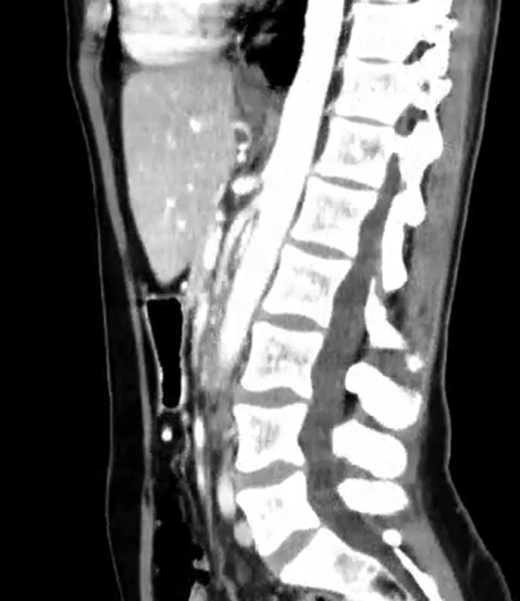

A 39-year-old Caucasian female patient presented to a General surgery outpatient clinic with complaints of epigastric pain, nausea, vomiting and weight loss for more than 5 years. The pain was worse after eating and with supine position. Vomiting was usually initiated 3–4 h after meals and consisted of undigested food. She had no significant prior medical history. On examination, the patient was extremely emaciated, with normal vital signs but with a distended abdomen and fullness over the epigastrium. She had already done an upper endoscopy that only showed gastric stasis. Abdominal ultrasound revealed a reduced angle between the AA and SMA (Fig. 1). An upper GI contrast study was requested, which revealed a distended stomach with delayed gastric emptying and lagging of contrast at the third portion of the duodenum (Fig. 2). Abdominal computed tomography (CT) scan was then performed. It demonstrated a severe distension of the stomach and proximal portions of the duodenum with constriction of the third part of the duodenum between the AA and SMA, with a reduced angle (11°) and shortened distance (4–5 mm) between these two arteries (Figs 3 and 4). These findings were suggestive of an aortomesenteric clamp. Hence, based on known findings, the diagnosis of Wilkie’s syndrome was established.

CT scan—axial CT image of obstruction of the third portion of duodenum between AAA and SMA.